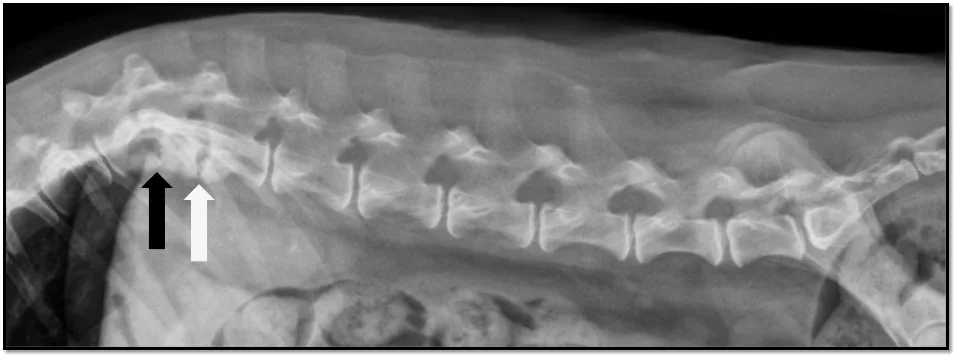

Plain lateral thoracolumbar spinal radiography was performed to pursue an etiology for the spinal pain.

FIGURE Lateral radiograph

The T12-T13 (black arrow) and T13-L1 (white arrow) vertebral end plates were sclerotic and irregular with areas of lysis, and the T12-T13 intervertebral disk space appeared collapsed with possible subluxation of the articular processes. A second view would be needed to evaluate lateral subluxation.

Radiographs were suggestive of discospondylitis. Discospondylitis is most commonly diagnosed in young, large-breed hunting dogs but should be considered in any patient with acute, focal spinal pain with or without myelopathy. Bacterial and fungal organisms can cause discospondylitis. Staphylococcus spp, Streptococcus spp, and Pasteurella spp are commonly reported bacterial etiologies; Aspergillus spp is the most commonly reported fungal etiology in dogs. Cultures of urine, blood, or disk material may aid in diagnosing the causative agent.